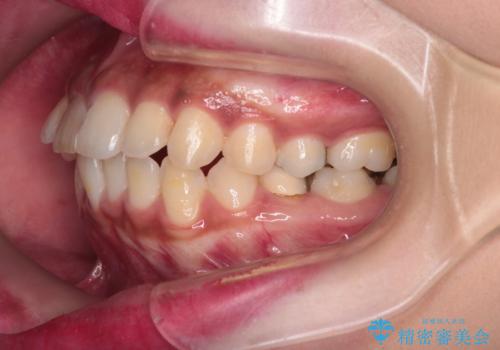

前歯の突出感を改善|上下4本の抜歯と審美ワイヤー矯正でバランスの取れた口元へ

- 患者様は、前歯の突出感を気にされて来院されました。診察の結果、歯列のスペースが不足しており、前歯を後方へ移動させるには抜歯が必要と判断。上下の小臼歯4本を抜歯し、目立ちにくい審美ワイヤー矯正(白いワイヤーと透明ブラケット)を使用して治療を行う計画を立てました。

抜歯によって前歯を下げるためのスペースを確保。その後、審美ワイヤー矯正を用いて、歯列全体のバランスを整えながら前歯を後方へ移動させました。治療後は、横顔のラインが整い、自然な口元になったことで、見た目も噛み合わせも改善しました。患者様からは「口元がすっきりして、自信を持って笑えるようになった」と喜びの声をいただきました。